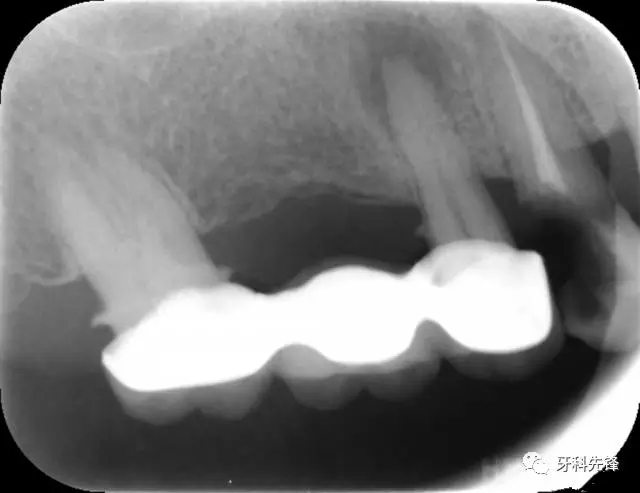

圖8治療術(shù)后X光片

640.webp (10).jpg

X 示:15  根管透射,根尖有陰影

14  根管阻射,恰填,無異常

46  根管阻射,恰填,根分叉骨密度降低,近中根尖陰影較大

圖18 14  15   三個月后X光片(根尖陰影減?。?/p>

640.webp (22).jpg